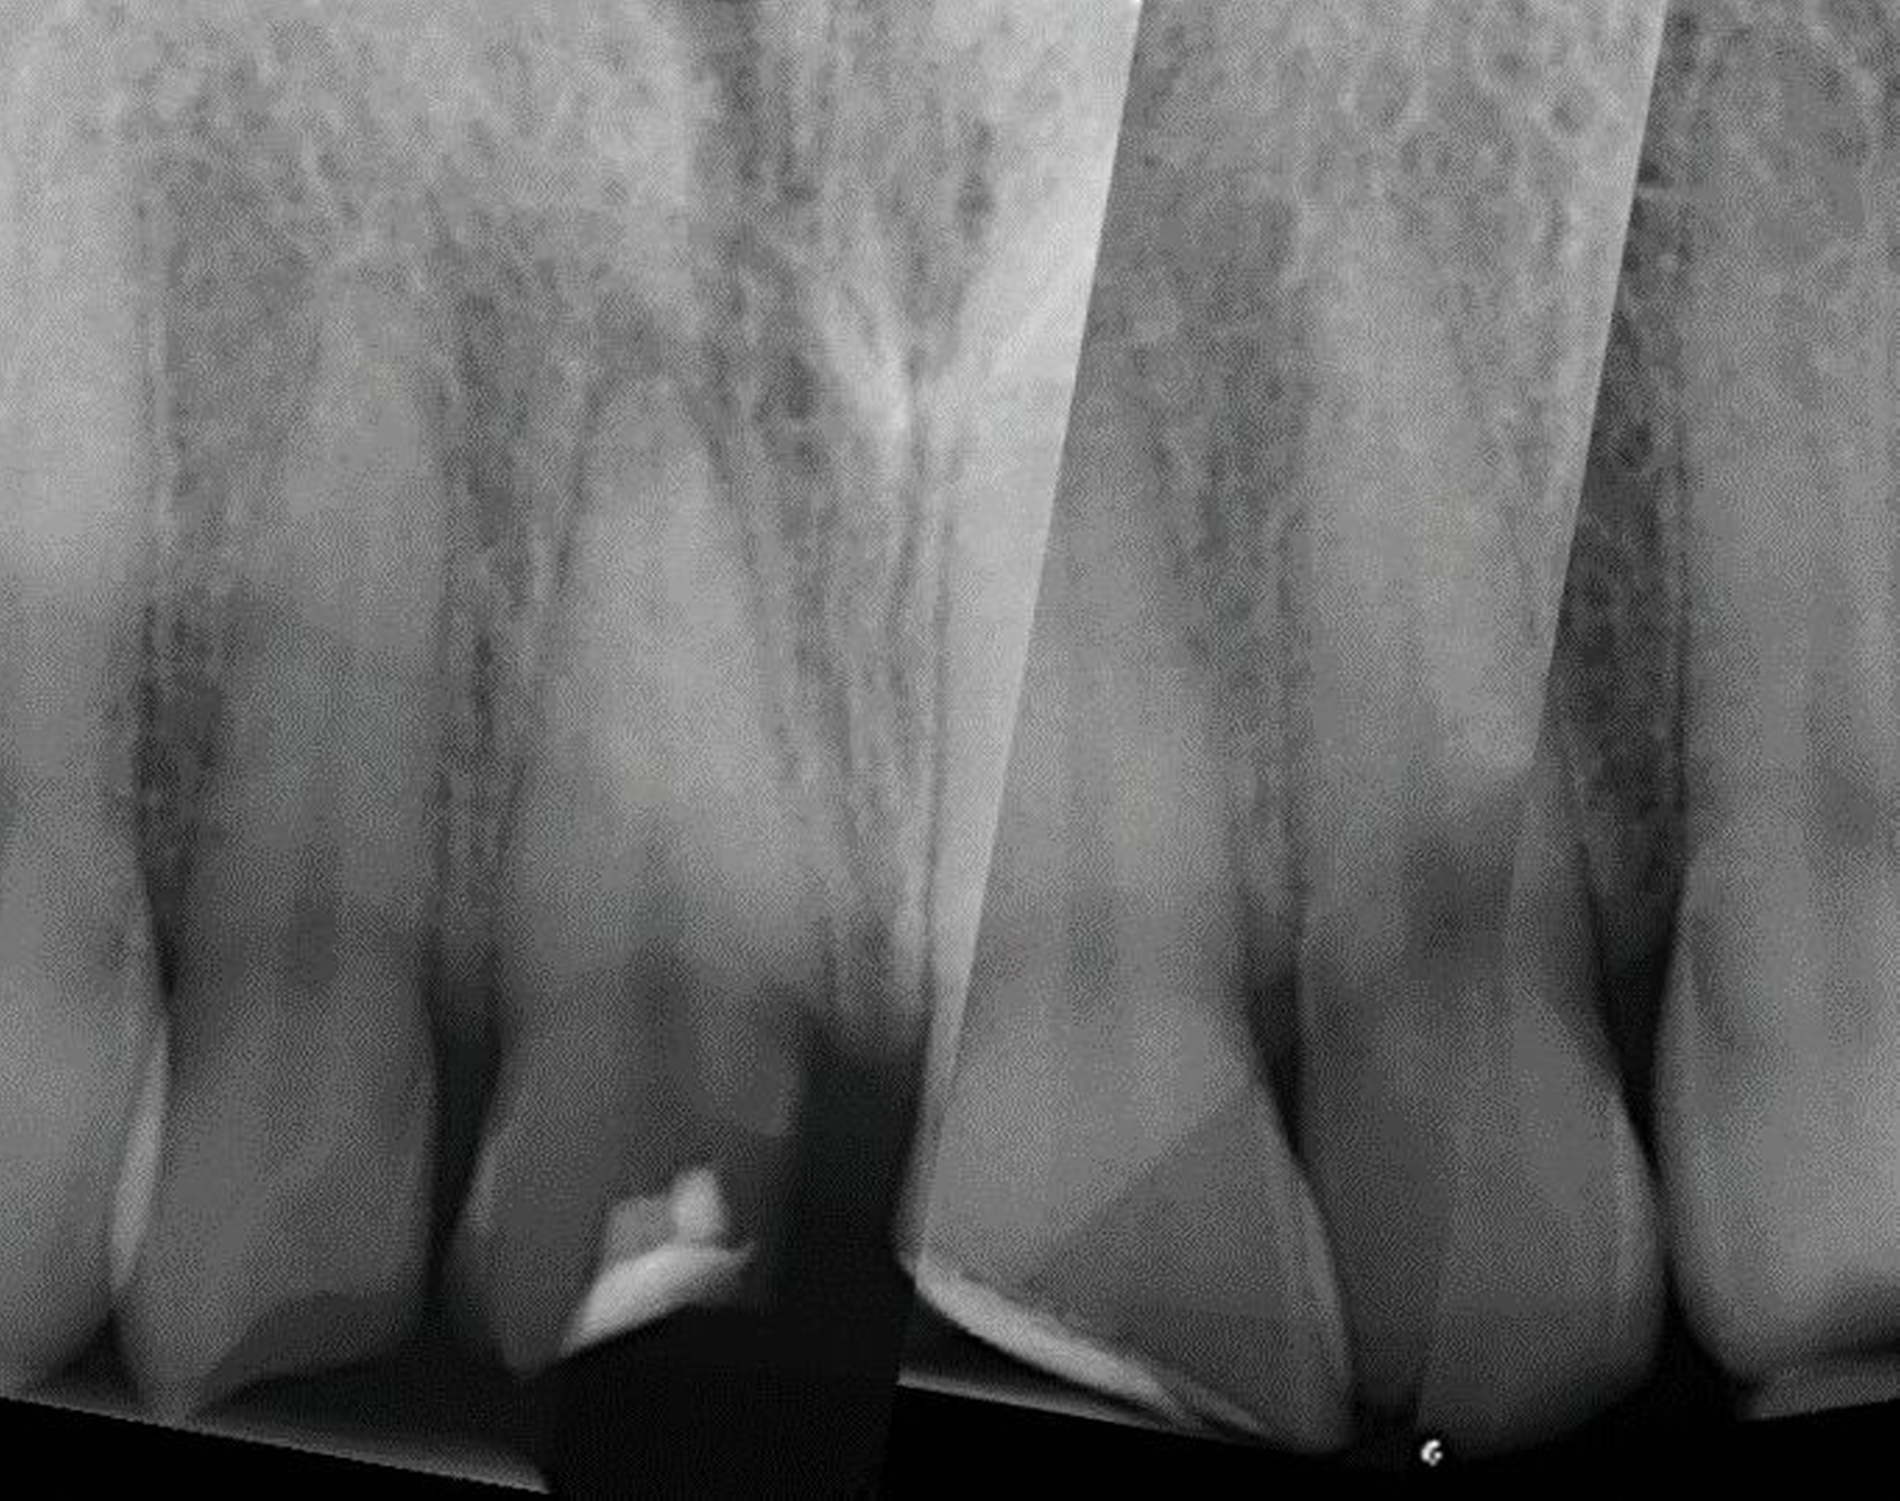

Ein 22-jähriger Patient stellte sich im Februar 2020 im zahnärztlichen Notdienst der Klinik für Zahn-, Mund- und Kieferkrankheiten Mainz vor. Aufgrund einer Synkope war er mit dem Oberkiefer auf den Rand einer Badewanne gestürzt. Intraoral zeigte sich der Zahn 12 mit einer Schmelz-Dentin-Fraktur ohne Pulpabeteiligung (unkomplizierte Kronenfraktur), der Zahn 11 mit einer Kronen-Wurzel-Fraktur mit Pulpabeteiligung und der Zahn 21 mit einer Schmelz-Dentin-Fraktur mit Pulpabeteiligung (komplizierte Kronenfraktur). Die Zähne zeigten keine erhöhten Lockerungsgrade oder Dislokationen (Abbildung 2). Herausfordernd für die weitere Versorgung war der Frakturverlauf an Zahn 11, an dem die Frakturkante palatinal tief subgingival und mesio-palatinal auch subkrestal lag. Röntgenologisch konnte die klinisch gestellte Verdachtsdiagnose bestätigt und eine Wurzelfraktur ausgeschlossen werden (Abbildung 3).